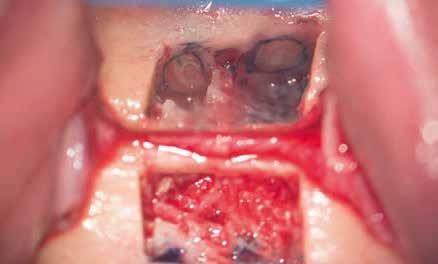

CÉLZOTT ENDODONCIAI MIKROSEBÉSZET

1. a-n. ábrák: Preoperatív CBCT-felvétel a bal alsó 6-os (3.6) fogról. Az axialis (a), coronalis (b) és sagittalis (c) nézeteken a mezialis és distalis gyökerek apicalis harmada körül sugáráteresztő zóna és ép buccalis corticalis csont látható. Egy olyan sablont terveztünk, amely jelezte a csontablak határait az apicalis terület pontos elérése érdekében (d). A mikrosebészeti bevatkozás során a sablont a helyére illesztettük (e), a csontablak határait megjelöltük (f) egy Piezotome CUBE LED kézi-darabba fogott fűrésszel, majd kivágtuk és eltávolítottuk (g és h) az apicalis területhez történő hozzáférés, illetve a mezialis és distalis gyökerek rezekciójának, retrográd preparációjának és retrográd gyökértömésének elvégzése érdekében (i). Végezetül a csontablakot visszaillesztettük és kollagén szivaccsal stabilizáltuk (j). A műtét után közvetlenül készített röntgenfelvétel a 3.6-os fogról (k). A kétéves kontroll során készített CBCT-felvétel: axialis (l), coronalis (m) és sagittalis (n) nézetek.

Esetbemutatás (1.)

Egy 63 éves páciens korábban már kezelt bal alsó első nagyőrlőfogából (3.6) eredő mérsékelt fájdalom miatt kereste fel rendelőnket. A kórtörténetében panasza szempontjából releváns információ nem szerepelt. Az elkészült CBCT-felvételen a korábbi kezelések során észre nem vett, jelenleg feltáratlan meziobuccalis csatornát, valamint a mezialis és distalis gyökerek körül kialakult periapicalis elváltozást, és ezt a léziót borító intakt buccalis corticalis csontlemezt láttunk.

A fog revideálását és újbóli gyökértömését két ülésben végeztük el. A régi gyökértömés eltávolítását, valamint mindhárom gyökércsatorna megmunkálását és fertőtlenítését követően kalcium-hidroxid alapú gyógyszeres zárást helyeztünk a gyökércsatornákba. A gyökértömés egy héttel később került behelyezésre. A páciens panaszai két hónap elteltével sem szűntek.

Klinikai vizsgálat során vertikális kopogtatási érzékenységet jelzett. A fog körül mérhető szondázási mélység és a fogmobilitás fiziológiás volt. A CBCT-felvételen nem észleltünk a csontos regeneráció megindulására utaló jeleket (1. a–c. ábrák). A korábban gyökérkezelt, gyökértömött és revideált 3.6-os fog esetében az alábbi diagnózis került felállításra: periodontitis periapicalis symptomatica. A panaszokat okozó fog további ellátása során navigált endodonciai mikrosebészetet kívántunk alkalmazni. Az alsó állcsontról intraorális szkent (TRIOS, 3Shape) készítettünk, és a felszíni topográfiát tartalmazó STL fájlt, valamint a CBCT-felvétel készítése során nyert DICOM fájlokat a Blue Sky Bio szoftver segítségével egyesítettük. A sebészi sablon megtervezésére az így kapott háromdimenziós képet használtuk. A sablon kialakítása során arra törekedtünk, hogy a sablon egyértelműen meghatározza a gyökércsúcsi terület eléréséhez szükséges csontablak határait (1. d. ábra)

A beavatkozás során helyi érzéstelenítésben teljes vastagságú mucoperiostealis lebenyt képeztünk, és a sablon segítségével bejelöltük a preparálandó csontablak határait. Az ablak széleinek megfelelően Piezotome CUBE LED kézi-darabbal (ACTEON) a kortikális teljes vastagságában vágást ejtettünk, majd az így kapott csontlemezt (ablakot) eltávolítottuk (1. e–h. ábra), és ezt követően steril fiziológiás sóoldatba helyeztük. A rezekció elvégzését követően (1. i. ábra) a mezialis csatornákat ultrahangos eszközök segítségével (NSK) retrográd irányból preparáltuk, majd az így kialakított mélyedésbe retrográd gyökértömést készítettünk. A tömés anyagául az EndoSequence BC RRM Fast Set Putty-t (Brasseler) választottuk. A tömés elkészítését követően a csontablakot visszaillesztettük, és a stabilizálása érdekében a vágásoknak megfelelően kialakult résekbe kollagén szivacsokat (Collagen Tape, Zimmer Biomet) helyeztünk (1. j-k. ábra). A lebenyt 6/0-s Prolene varratokkal (Corpaul) rögzítettük.

A kétéves kontroll során elvégzett klinikai és radiológiai vizsgálat (CBCT-felvétel) a periapicalis elváltozások megszűnését és a corticalis csontállomány tünet- és szövődménymentes gyógyulását